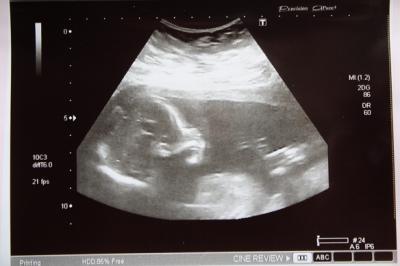

So meine Lieben! Jetzt will ich doch auch mal berichten, was hier bei mir im Bauch so alles los ist! Was euch sicherlich als erstes interessiert, Pünktchen ist gesund und munter und auf den Punkt genau entwickelt. Sehr aktiv turnte es im Bauch rum und die Ärztin mußte ordentlich rumschallen um mal nen vernünftigen Blick auf die Nabekschnur zu werfen. Größe liegt bei 19/20 cm und das Gewicht bei etwa 260g. Ich konnte soooooo viel sehen, das war schön. Ach, euch interessiert noch etwas?!?!?! Doch nicht etwa das Geschlecht?!?!!?! Hmmm, erstaunlich wie gut man das doch erkennen konnte! Das es sich tatsächlich um Schamlippen handelt und nicht um einen Penis! Jajajajjajaaaaaa, ein Mädchen!!!!!!!!!!!! GLG von einer glücklichen Wiebke